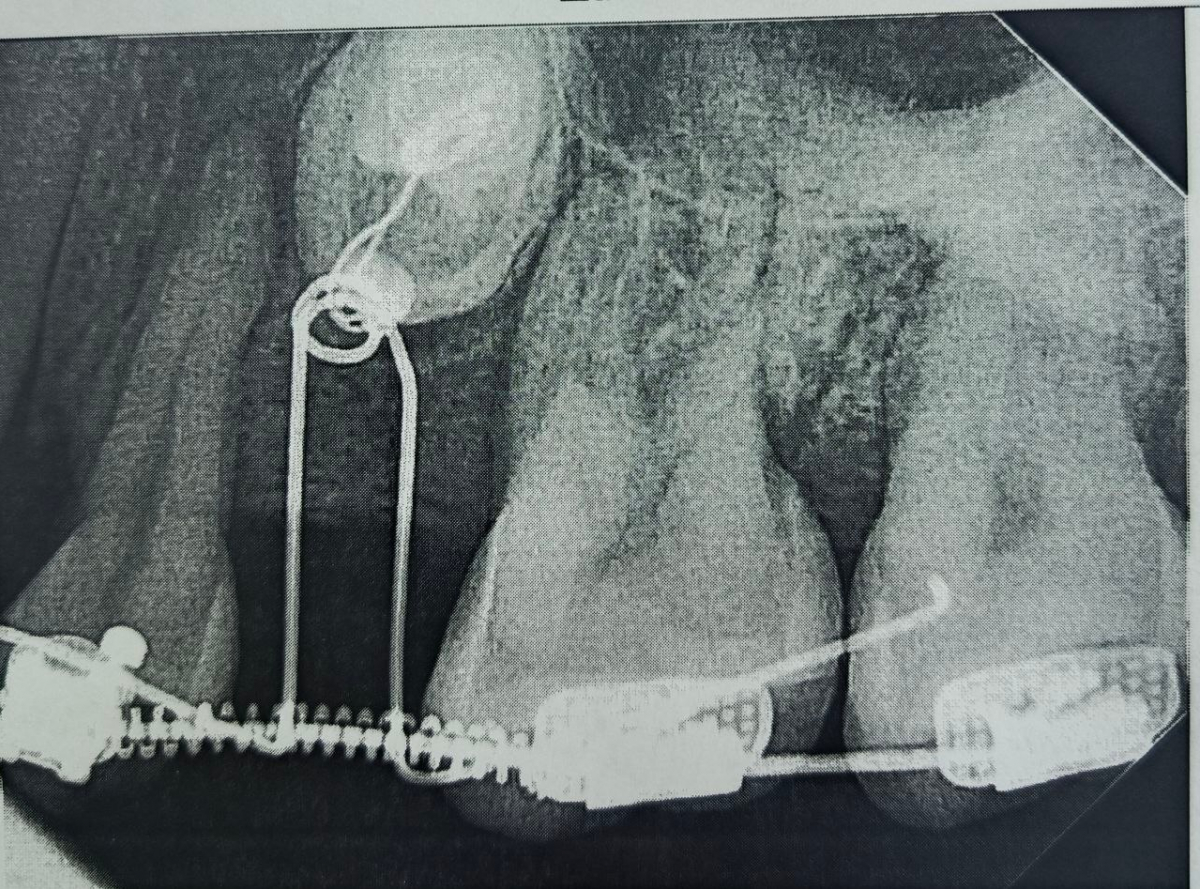

Когда пространство было подготовлено, хирурги провели операцию: раскрыли десну, чтобы обнажить коронки непрорезавшихся зубов, и зафиксировали на них специальные ортодонтические кнопки.

С помощью миниатюрных пружин и рычагов, подключенных к брекет-системе, зубы начали медленное движение.

На сегодняшний день один зуб уже полностью вышел из костной ткани и занял свое законное место. Второй успешно проходит последний барьер - кортикальную пластинку челюсти - и вскоре тоже встанет в ряд.